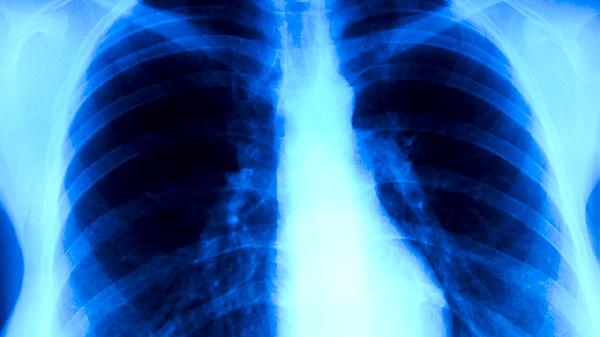

肺結(jié)核發(fā)病后有什么癥狀

肺結(jié)核發(fā)病后的癥狀主要有咳嗽、咳痰、咯血、胸痛、發(fā)熱等。肺結(jié)核是由結(jié)核分枝桿菌感染引起的慢性傳染病,早期癥狀可能較輕,隨著病情進(jìn)展癥狀會(huì)逐漸加重。